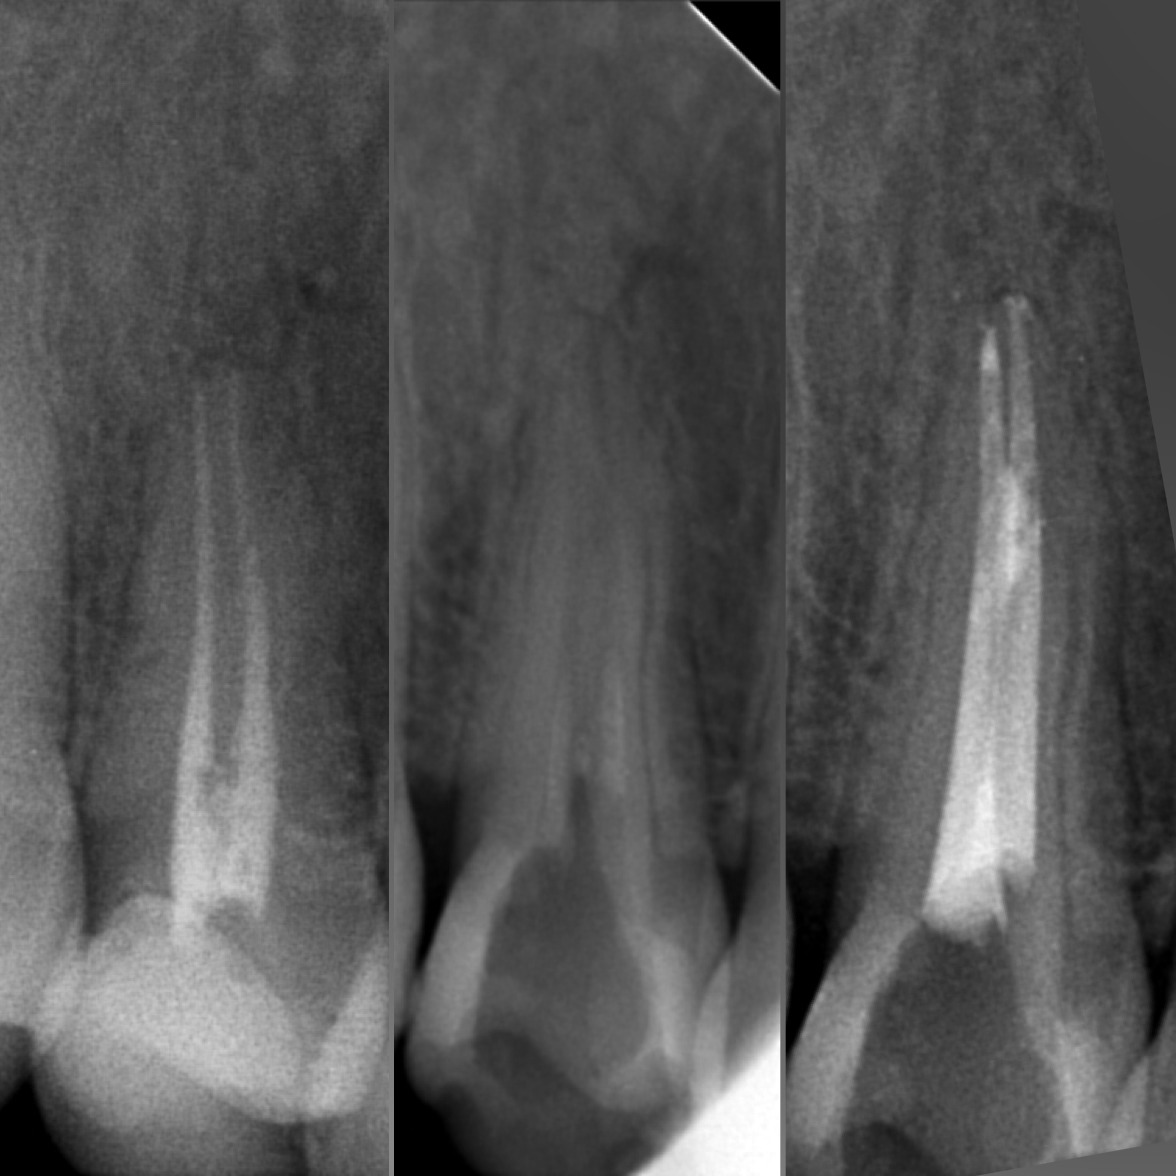

• Диагностика и лечение кариеса и его осложнений (пульпиты, периодонтиты)

• Эндодонтическое лечение корневых каналов с использованием стоматологического микроскопа